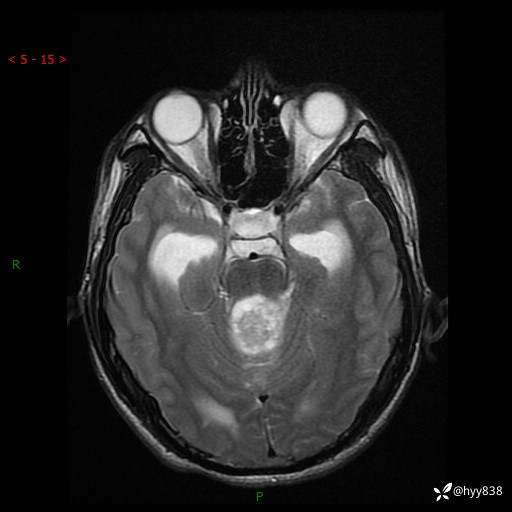

性别:男

年龄:17岁

简要病史:头痛伴间断性呕吐1月余,外院CT提示颅脑占位

颅脑MRI平扫+增强